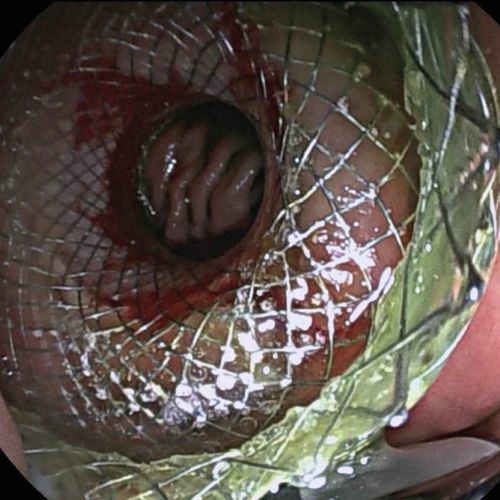

Schritt 4: Nun wird der LAMS (Abbildung 2) freigesetzt. Erst erfolgt das Öffnen der jejunalen Seite, danach wird das gesamte System so weit wie möglich an das Endoskop gezogen, was dazu führt, dass das Jejunum dem Magen anliegt. Dann wird die zweite Stenthälfte im Magen entfaltet.

Schritt 5: Das Lumen des LAMS wird dann mit einem Ballonkatheter durch das Endoskop dilatiert (6, 7), was zu einer weiteren Verkürzung des Stents führt (Abbildung 3). Als Lagekontrolle fließt das Indigokarmin durch den Stent in den Magen ab und es kann direkt durch den Stent in die gefüllte Jejunalschlinge geblickt werden (Abbildung 4).

Abbildung 4: Endoskopisches Bild mit liegendem LAMS. Beim Blick vom Magen aus durch den LAMS zeigen sich Dünndarmfalten.